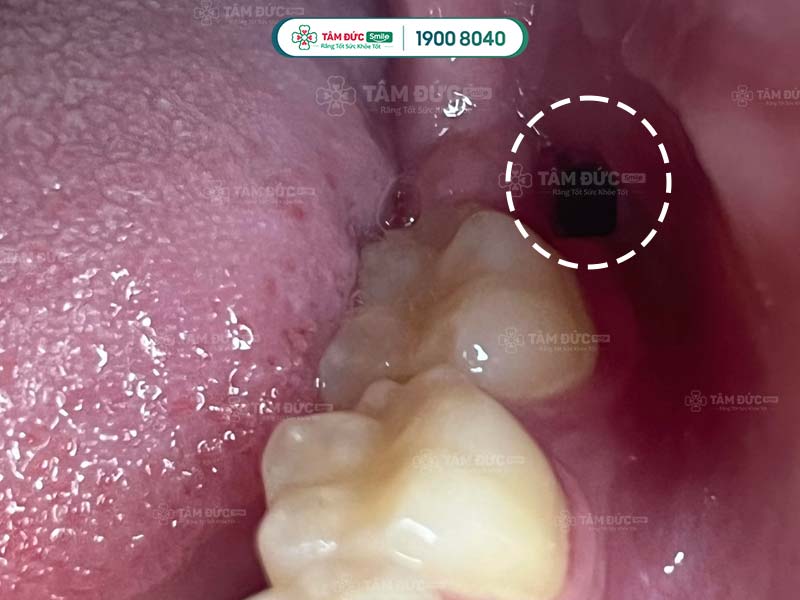

1.1. Nhổ răng khôn 2 tuần vẫn đau do nhiễm trùng

Khoang miệng luôn tồn tại lợi khuẩn và hại khuẩn. Khoảng 24h sau khi nhổ răng, chúng bắt đầu xâm nhập vào các mô bị tổn thương. Tiếp đó, chúng phát triển và gây hại ở vùng niêm mạc lợi, gây nên tình trạng nhiễm trùng. Nhiễm trùng là nguyên do hàng đầu gây ra tình trạng nhổ răng khôn 2 tuần mà vẫn đau.

Dụng cụ nhổ răng khôn không được khử trùng dễ dẫn tới nhiễm khuẩn

Chính những lý do trên đây đã làm Quý khách nhổ răng khôn 2 tuần vẫn đau. Để xác định chắc chắn mình có đang bị nhiễm trùng sau khi nhổ răng khôn hay không, Quý khách hãy dựa vào các dấu hiệu sau đây.

- Mùi hôi miệng khó chịu.

- Miệng có vị đắng.

- Có dấu hiệu sốt cao.

- Cơn đau nhức tái đi tái lại thường xuyên dù đã dùng thuốc giảm đau.

- Nướu, cổ và hàm bị sưng tấy.

- Quai hàm có cảm giác đau.

- Khô ổ răng.

Viêm nhiễm kéo dài có thể gây ra nhiều biến chứng nguy hiểm. Ngay khi phát hiện nhiễm trùng, Quý khách hãy gặp bác sĩ để được điều trị càng sớm càng tốt.